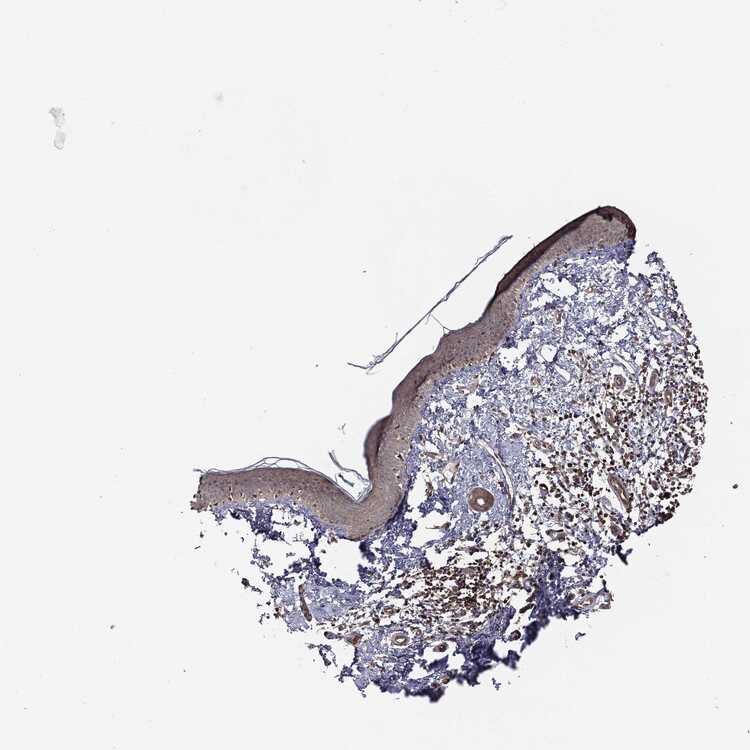

SKIN 2 - Antibody stainingi

Antibody staining in the annotated cell types in the current human tissue is reported as not detected, low, medium, or high, based on conventional immunohistochemistry profiling in selected tissues. This score is based on the combination of the staining intensity and fraction of stained cells.

Each image is clickable and will lead to virtual microscopy that enables deeper exploration of all samples and also displays staining intensity scores, fraction scores and subcellular localization as well as patient and tissue information for each sample.

Antibody CAB069425Antibody CAB080053Antibody CAB080065Antibody CAB080070Antibody CAB080081Antibody CAB080095Antibody CAB080097

Epidermal cells MediumMediumNot detectedLowNot detectedMediumMedium